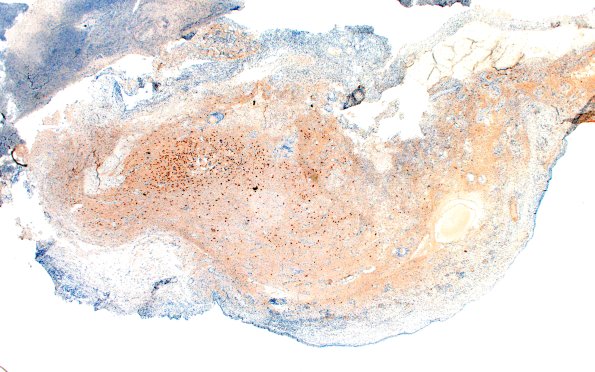

6D1Nasal glioma (Case 6) A2 Neu-N 2X

6D1,2 There are patches of neurons which are outnumbered by glia. (NeuN)